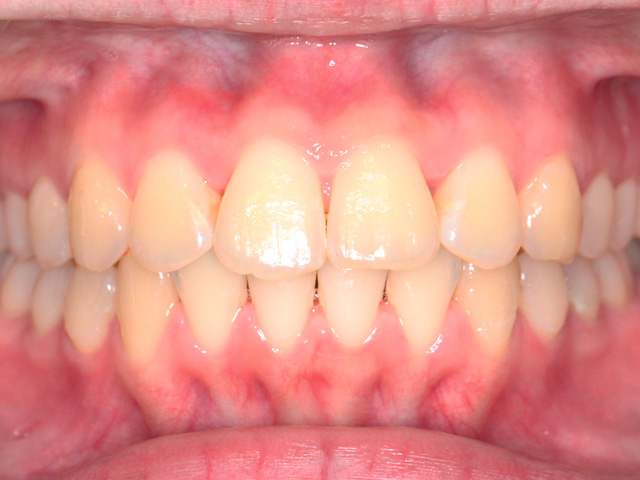

正面の画像です。上下の前歯に叢生が見られます。

上下とも中切歯(中央の前歯)よりも側切歯(中央から2番目の前歯)が内側に位置しています。特に左下の側切歯(中央から2番目の前歯)の叢生ははなり重度の状態です。